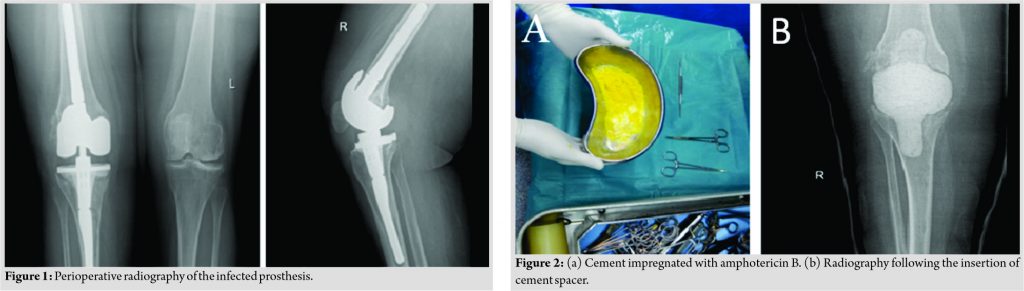

However, 9 months following the two-stage revision TKR, the patient presented with the right knee pain, swelling, and hotness. The physical examination revealed redness, hotness, restricted range of movement, and tibial loosening which called for the admission of the patient. The patient’s complete blood count, kidney function tests, liver function tests, and chemistry were all sent for laboratory analysis refer to Table 1 and Fig. 1whichshow the prerioperative radiographs. Right knee soft-tissue excision showed fibrofatty tissue with inflammatory infiltrate and fibrin. Necrotic bone periodic acid–Schiff (PAS) stain was negative for fungal spores and pseudohyphae. Right knee synovial fluid aspirate showed sheets of neutrophils in hemorrhagic background. PAS stain is negative for fungal spores and pseudohyphae, but culture of the joint aspirate showed growth of “C.parapsilosis.” A repeated culture confirmed the presence of the fungal infection. During this admission, the patient underwent the first stage revision of TKR with removal of the infected prosthesis and placement of amphotericin bimpregnatedcement spacer (Fig. 2) and received capsofungin 50mg, fluconazole 200 mg, imipenam+ cilastin 500mg, ceftriaxone 1g, levofloxacin 500mg, and vancomycin 500mg for 40 days and then was discharged on fluconazole 150 mg 1*1 for 6 weeks. Knee aspirate culture demonstrated no fungal presence 2 weeks post-anti-fungal treatment.

Three months following the placement of amphotericin B impregnated cement spacer, the patient was admitted for the second stage TKR with removal of the cement spacer and placement of the new knee prosthesis after confirming the sterility of the aspired knee culture during the hospital stay, the patient was on imipenem + cilastatin 500mg, amphotericin B 50mg, fluconazole 150 mg capsules, vancomycin 500mg, and cefuroxime 750mg. The patient was discharged on fluconazole 150 mg 1*2 for at least 12 months. During the subsequent period, the patient was improving and gradually regaining the range of motion and her X-ray at 8thmonths post-operative is presented in Fig. 3.The patient was seen in the clinic for regular checkup and serial laboratory testing every 4 weeks.. However, after completion a period of 9 months out of the planned 12 months of oral Fluconazole, the patient developed skin rash and stopped the medication.